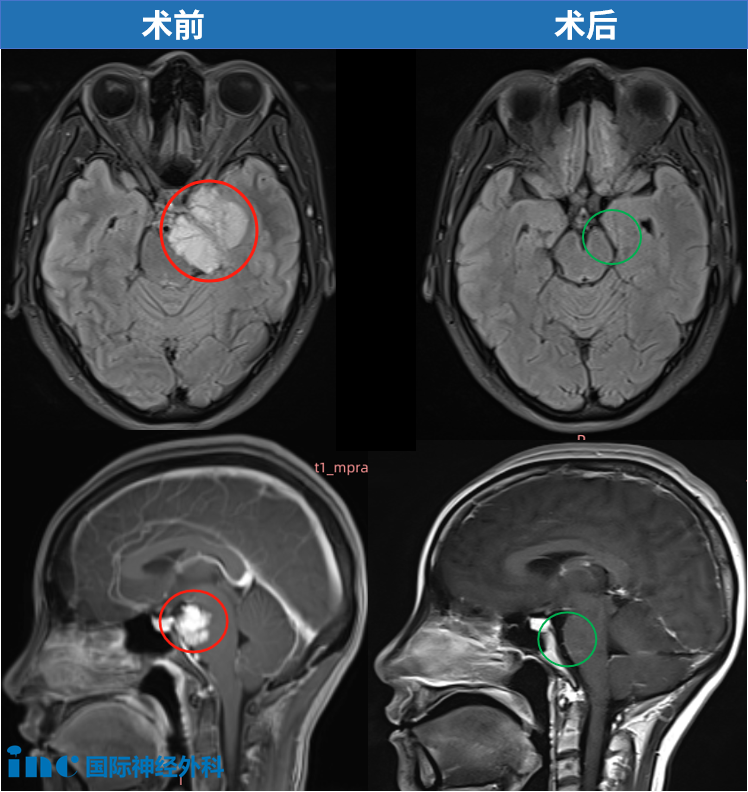

而天坛医院与福洛里希教授的合作,为她带来希望。北京天坛医院手术如期进行——复杂的岩尖区、4.5cm左右的脑膜瘤,“生命禁区”脑干和左颞叶均受压。刚查出时,无任何症状,然而到术前检查竟然发现左眼视力更是降至微弱的0.1.仅一个月时间……幸运的是,这台手术不仅保护了她的爱美之心、没有剃头,更是为她成功切除肿瘤,颅神经(尤其是动眼神经、滑车神经、三叉神经)被保护得很好。

但当我将这个消息告诉家人后,他们都认为无论肿瘤是否良性,长在脑子里就像个定时炸弹,必须处理。在他们的建议下,我开始咨询多位专家。这时我才知道肿瘤已经很大了(45x38x32mm),所有医生都建议尽快手术,我才意识到问题的严重性。

2024年12月9日,福教授在北京天坛医院国际部为我做了脑膜瘤手术。到现在术后快半年了,还差两周左右。